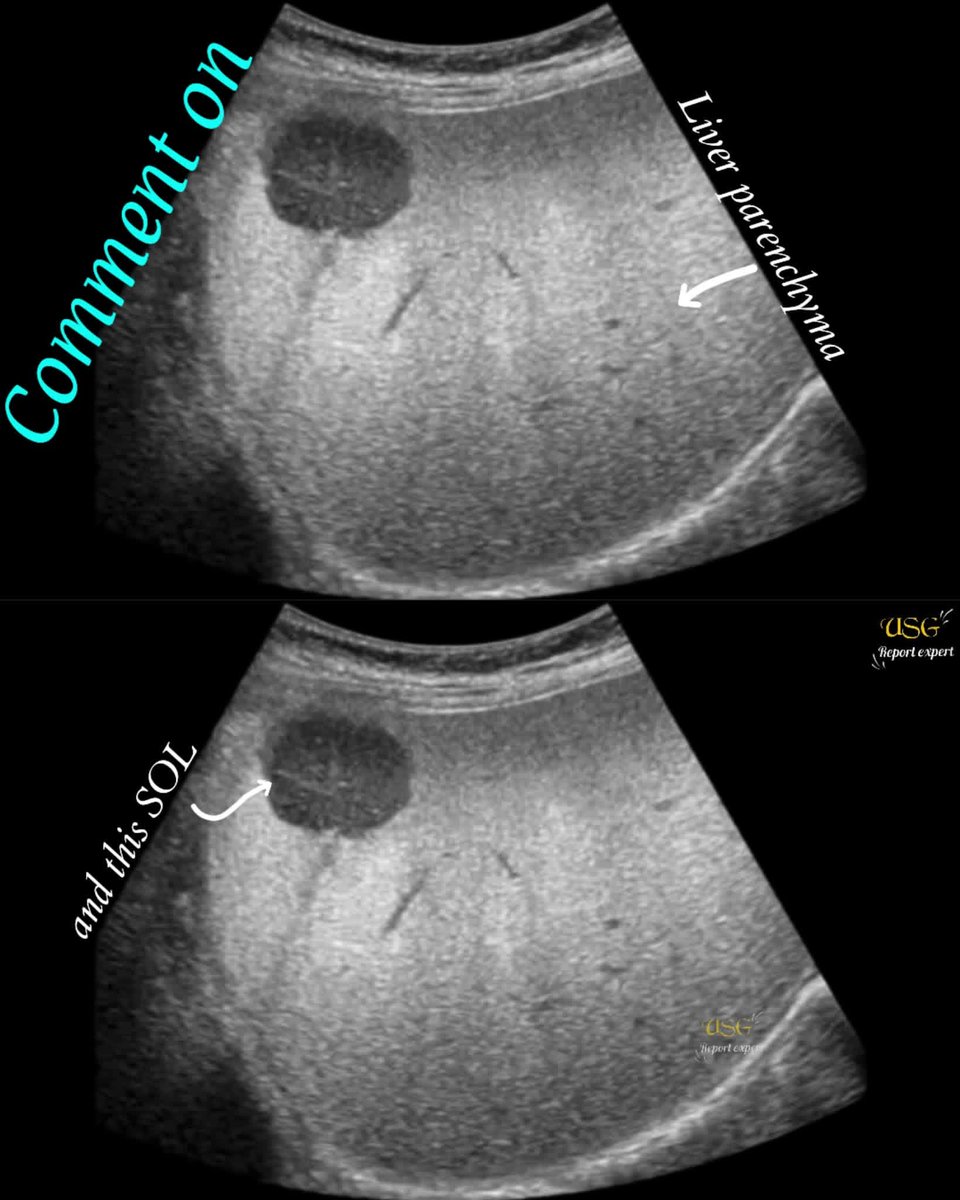

راح يكون في بالي تشخيصين:

إذا كانت هناك حرارة شديدة وترافقت مع ارتفاع CRP و WBC برجح خراج كبدي.

أما اذا حرارة بسيطة مع فقدان وزن وتعب مزمن برجح سرطان كبدي.

والله أعلم.

This 44 years old male alcoholic patient history of RUQ pain and tenderness for 23 days || indigestion || vometing || fever #ultrasound #liver #medical #doctor #health #education #healthcare #lifestyle #disease #celiacdisease

@EchoTech_4 A well defined hypoechoic lesion is seen in the right lobe with irregular margins . No internal calcification is seen. Liver shows diffused echogenicity with reduced visualisation of intrahepatic vascular margins consistent with diffuse fatty infiltration

>>> Hepatic Abscess

This 44 years old male alcoholic patient history of RUQ pain and tenderness for 23 days || indigestion || vometing || fever